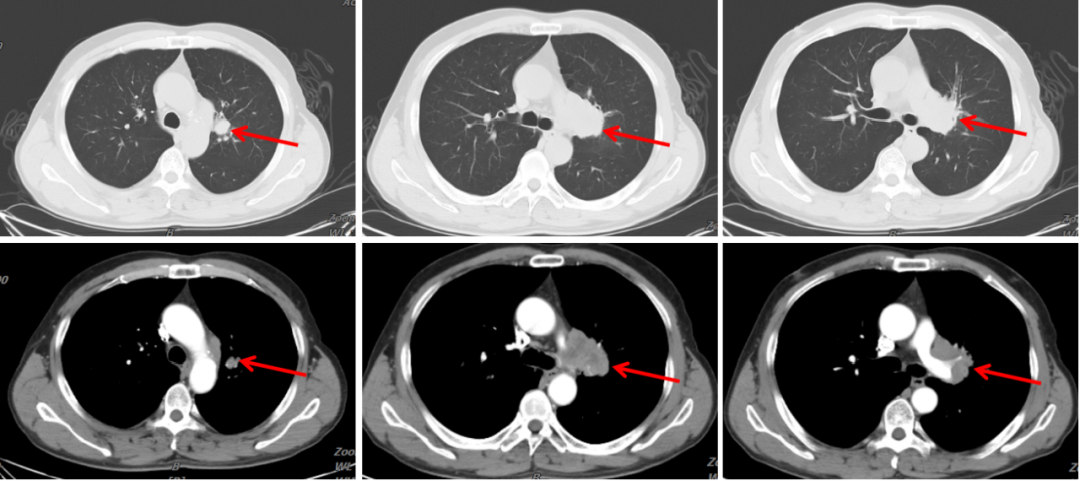

图3:2020年1月30日,治疗前胸部CT

图4:2020年1月30日,治疗前头颅MRI

病例二治疗经过

经患者充分知情同意并签署知情同意书后,考虑予以免疫联合化疗治疗。于2020年2月7日先行1周期EP方案化疗:“依托泊苷(VP-16)0.1g d1-4 + 卡铂500 mg d1,q3w,ivgtt”;于2020年2月6日至3月6日间行全脑放疗(46Gy/23f);于2020年2月28日起行免疫联合化疗:“替雷利珠单抗200 mg d1 + 依托泊苷 0.1g d1-4 + 卡铂500 mg d1,q3w,ivgtt”,至今已应用替雷利珠单抗治疗9周期。

(1)治疗2周期

疗效评价:PR。

图5:2020年2月6日至3月6日,行全脑放疗

图6:2020年3月20日,联合治疗2周期后胸部CT

图7:2020年3月25日,联合治疗2周期后头颅MRI

(3)治疗4周期

疗效评价:持续PR。

图8:2020年5月4日,联合治疗4周期后胸部CT

图9:2020年5月6日,联合治疗4周期后头颅MRI

病例二总结

本例患者为“左肺上叶小细胞癌(广泛期,cT3N1M1,IV期),伴左肺门淋巴结转移、多发脑转移”,考虑予以免疫联合化疗。为明确并监测患者可能出现的毒副反应,先予以患者1周期EP方案化疗,同时予以全脑放疗1个月。患者未出现明显不良反应,予以患者加用替雷利珠单抗免疫治疗2周期,疗效评价即达到PR,治疗6周期后疗效达到CR。随访至今PFS已超过7个月,疗效持续CR,安全性良好,患者可以耐受。